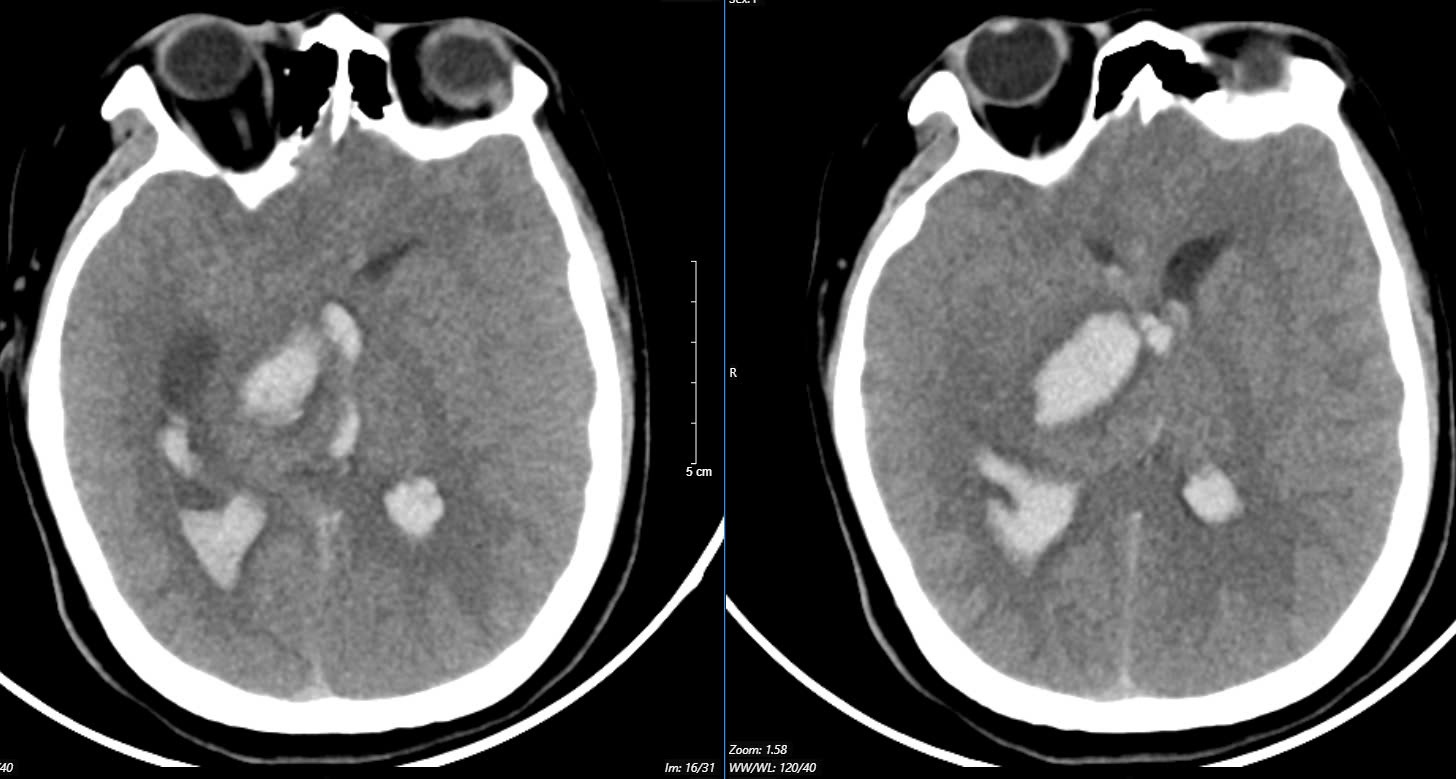

Bệnh nhân thứ 3 là nữ, 29 tuổi, tiền sử khoẻ mạnh. Bệnh nhân đến viện vì đột ngột đau đầu, tê tay, nôn nhiều vật vã. Tại bệnh viện tỉnh, bệnh nhân được chẩn đoán chảy máu não, các bác sĩ đã đặt ống nội khí quản thở máy rồi chuyển tuyến lên Trung tâm Đột quỵ, Bệnh viện Bạch Mai trong tình trạng ý thức hôn mê, Glasgow 6 điểm, thở máy, đồng tử bên phải giãn 4mm, tụt huyết áp, duy trì vận mạch.

Chụp MSCT mạch não cho thấy chảy máu não thuỳ đỉnh phải, chảy máu não thất do vỡ AVM ( điểm Spetzler Martin 2 điểm). Bệnh nhân đã được phẫu thuật lấy máu tụ và khối dị dạng. Tuy được điều trị tích cực nhưng di chứng để lại vô cùng nặng nề.

Sau một tháng điều trị, bệnh nhân chưa nhận thức được, liệt hoàn toàn nửa người trái…

Hình ảnh chụp MSCT mạch não: Chảy máu não thuỳ đỉnh phải, chảy máu não thất do vỡ AVM ( điểm Spetzler Martin 2 điểm) bệnh nhân nữ, 29 tuổi. Ảnh BVCC